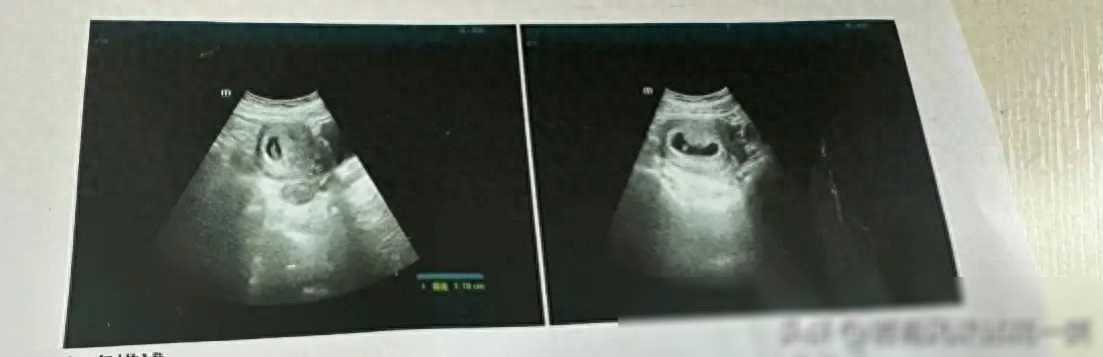

我决定去医院进行进一步的检查,确保孩子的健康。医生告诉我,我已经怀孕两个月了,胎儿的发育情况良好。